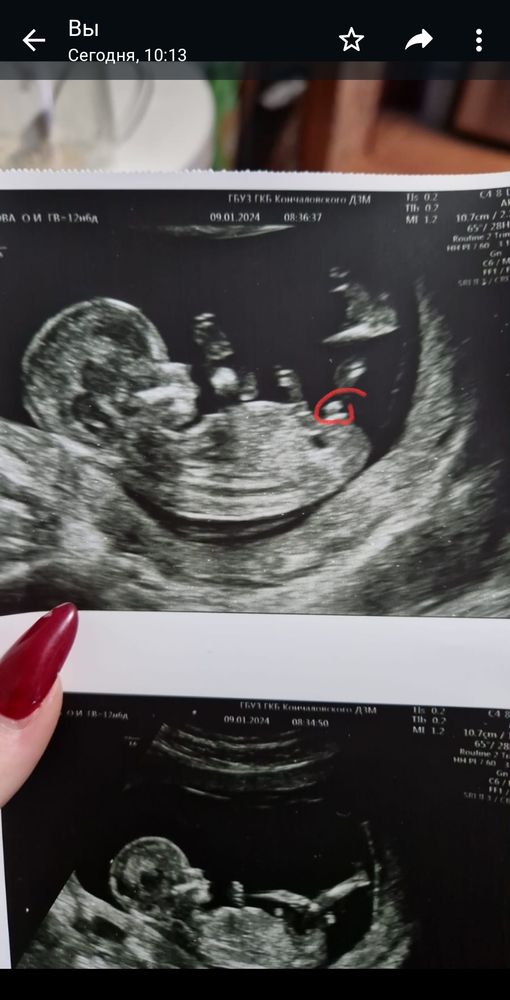

Девочки подскажите, узи было в 13 недель, врачь сказала на мальчика похоже. Типо если бугорок вверх торчит значит мальчик. Очень уж дочка братика ждёт. Второй скрининг через 10 дней, а мне не в терпеж, муж на платное запрещает идти, говорит что пойдём как положено, но а мне то любопытно очень.

Мальчик скорее всего. Там не только еще половой бугорок, но и мочевой пузырь как бы по диагонали от этого бугорка. Это вроде тоже как на мальчика указывает